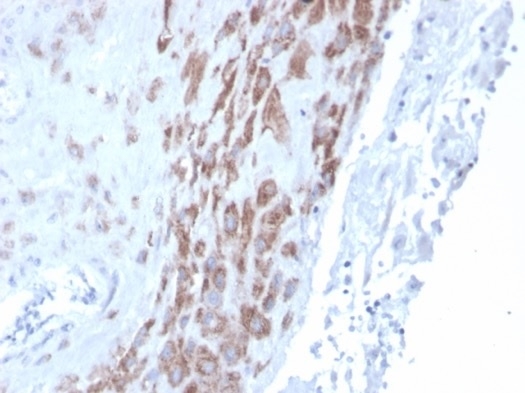

IHC analysis of formalin-fixed, paraffin-embedded human placenta. Staining using IDO2 antibody (IDO2/2639) at 2ug/ml in PBS for 30min RT.HIER: Tris/EDTA, pH9.0, 45min. Secondary: HRP-polymer, 30min. DAB, 5min.

Immunohistochemistry (Formalin-fixed): 1-2ug/ml for 30 minutes at RT. Staining of formalin-fixed tissues requires heating tissue sections in 10mM Tris with 1mM EDTA, pH 9.0, for 45 min at 95C followed by cooling at RT for 20 minutes